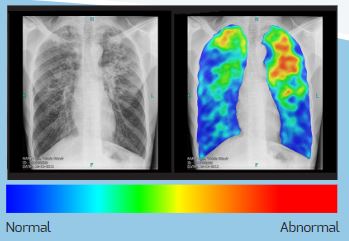

Computer-aided detection (CAD) software programs use artificial intelligence (AI) and deep learning techniques to analyse digital (not traditional film) chest X-ray images to detect and localize suspected radiographic abnormalities. These software programs are trained on large datasets (in some cases millions of Chest X-rays) and the quality and accuracy are constantly improving. CAD4TB is one of the CAD software programs used specifically to detect abnormalities associated with tuberculosis and has been shown to perform on par with experts (radiologists). CAD is has recently been endorsed by WHO for digital chest X-ray analysis for TB screening and triage in individuals aged 15 years and above.

The CAD4TB offline box is connected to validated digital X-ray systems to receive Posterior – Anterior (PA) Chest X-ray images. The software installed on the box analyses the Chest X-ray in less than one minute. The output is a colour heat map showing suspected abnormalities related to TB, and a score between 0 – 100 representing the overall likelihood of TB. A threshold score is chosen to determine which patients should be referred for a follow-up test, such as GeneXpert, to confirm TB diagnosis. CAD4TB does not provide information about non-TB diagnoses, in many situations human readers are still required to review the Chest X-rays.

Use of digital chest X-ray with CAD requires integration into TB screening and triage protocols. A critical aspect of implementation is the initial choice and calibration of a ‘threshold' score. The performance of CAD4TB is highly dependent on the demographic characteristics of the population and thus the choice of threshold score must reflect the local context. (i.e. CAD4TB is not just ‘plug and play'). As there are other important details as well as known limitations with regards to this technology, please contact diagnostic-network@msf.org for more information.